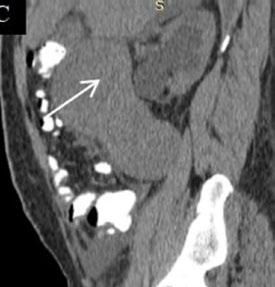

Creative Director

Tim Uden

Design Manager

Stacey White

Senior Designers

Owen Silcox

Tamara Kondolomo

Creative Artworker

Dillon Benn Grove

Designers

Shanjok Gurung, Fabio van Paris

Junior Designer

Helena Spicer